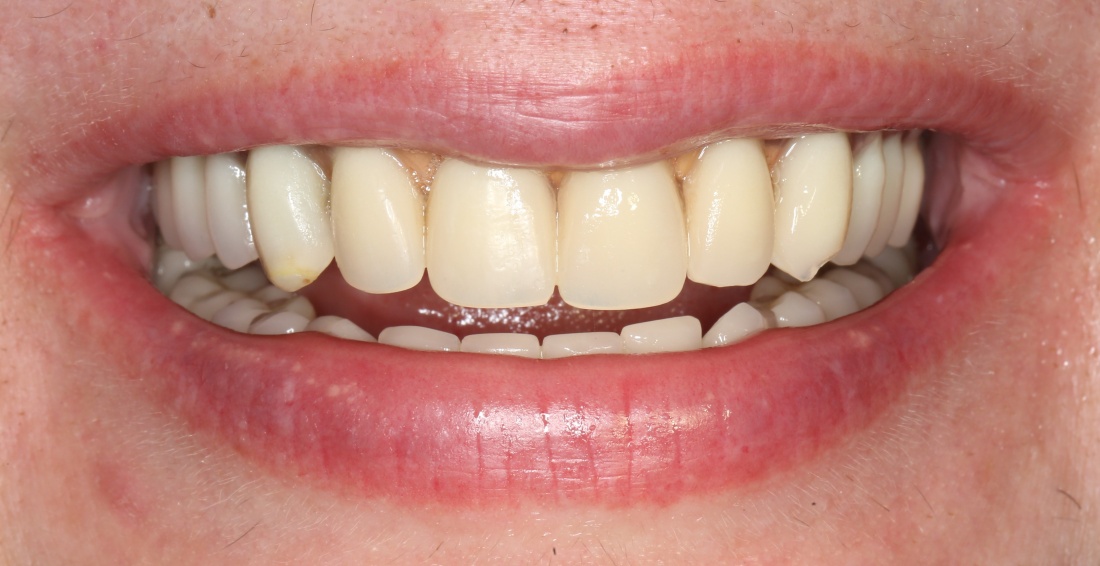

Рекомендации по установке имплантов. Для всех. Часть II.